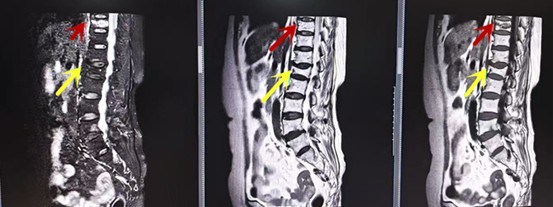

利器三:MRI(核磁共振)

MRI利于磁場(chǎng)和射頻脈沖使體內(nèi)的氫原子核發(fā)生磁共振現(xiàn)象而產(chǎn)生的圖像,對(duì)軟組織的分辨率很高,對(duì)于脊髓、椎間盤(pán)、神經(jīng)、血管、韌帶、骨髓、腰部肌肉及周?chē)浗M織有很好的顯示效果,可以清晰的顯示腰椎間盤(pán)突出對(duì)硬膜囊、神經(jīng)根壓迫程度,以及骨折是陳舊還是新鮮,同時(shí)在脊髓病變(如脊髓損傷、髓內(nèi)出血或腫瘤)、椎管內(nèi)膿腫/血腫、椎旁肌肉軟組織病變等方面也具有優(yōu)勢(shì),但是檢查時(shí)間較長(zhǎng),部分患者可能因體內(nèi)金屬植入物(如心臟起搏器、人工耳蝸等)而無(wú)法進(jìn)行檢查。

箭頭提示腰椎管內(nèi)腫瘤

紅色箭頭提示新鮮骨折,黃色箭頭提示陳舊性骨折